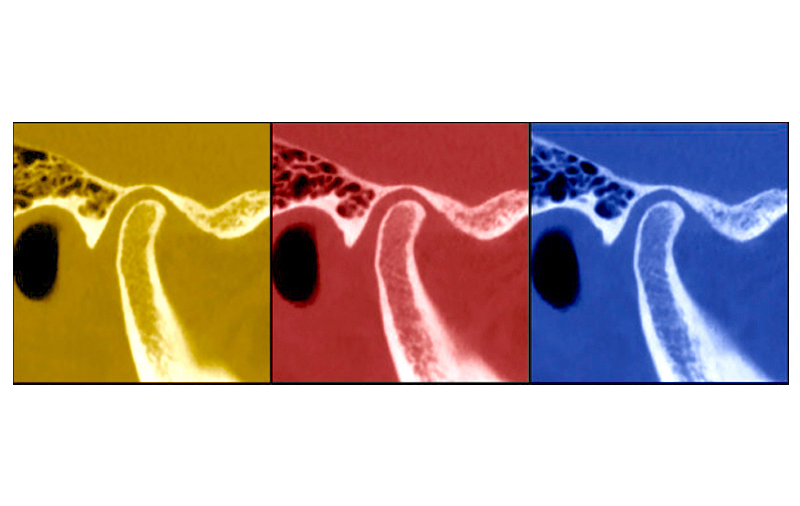

The article is written by the group of world-renown experts in TMJ. In their introduction, the authors touches upon the history of CR-CO controversy and mentions Ronald Roth who “played a pivotal role in merging the gnathological-prosthodontic philosophies into orthodontics”. Roth’s main idea was to establish an “ideal” condylar position in the glenoid fossa by the means of mechanical changes of occlusion. In 1970s, he described such a position as posterior and superior, but later, in 1980s, he frivolously changed it to anterior and superior. Today neither of Roth’s beliefs sound scientifically tenable. From CBCT and MRI studies, we now know that healthy individuals may have anterior, centric, or posterior condylar positions [2], whereas every third healthy individual has some form of disk displacement [3].